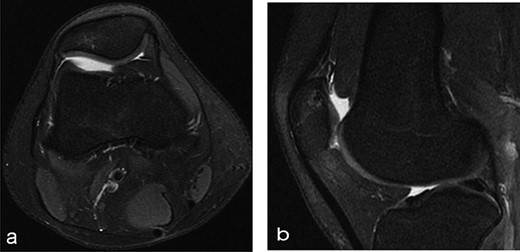

A 14-year-old female dancer presented with increasing right knee pain and functional disability without any trauma. Her pain was retropatellar pain that often radiated medially or laterally from the patella, exacerbated by climbing stairs, running and squatting. She was unable to perform any sports activities. Examination revealed peripatellar tenderness and crepitus, full range of motion and the knee was stable. Radiological examination included both MRI and computed tomography of the knee were performed at the beginning. MRI showed osteochondritis dissecans at the area at the superolateral facet of the patella in the deep subchondral area as shown in Fig. 1. This was appropriately treated conservatively with 6 months of reduced load and protected weight bearing without relief of symptoms. She quit sport activity for 2 years and then another MRI was performed Fig. 2. After 2 years we opted for adipose-derived mesenchymal stromal cells (AD-MSCs) intra-articular therapy according to the procedure described by Tremolada et al. [9]. The patient’s parents were given written information regarding the use of AD-MSCs therapy, including relative risks of this therapy and also relevant treatment alternatives that could otherwise be explored. Postoperative radiological evaluation was performed at 6 months and 12 months after AD-MSCs procedure as shown in Figs. 3 and 4. Postoperative clinical evaluation was performed using IDKC, Lysholm and Tegner scores (Table 1). After surgery, patients began a McConnell program of lateral retinacular stretching, patellar taping and vastus medialis obliquus muscle exercises. The patient was encouraged to swim and cycle to reduce impact loading. Using AD-MSC, she reported a complete relief of pain after 1 year from the procedure. Routine MRI follow-up 2 years later showed evidence of appreciable improvement in cartilage volume and osteochondral architecture at the site of injury. Early MRI T2 mapping at 6 months indicated that the area of cartilage regeneration exhibited high water content suggestive of immature cartilage or fibrocartilage morphology. Later T2 mapping at 18 months after the procedure, indicated progressive maturation of cartilage from deep to superficial layers with more hyaline like cartilage morphology. Limitations of the study are lack of arthroscopic intra-articular visualization and classification of the patella lesion.

Radiographs after 2 years at 16 years old (a) sagital T2-weighted MRI sequences (b) sagital T1-weighted MRI sequences showed the area was still the same at the superolateral facet of the patella in the deep subchondral area.